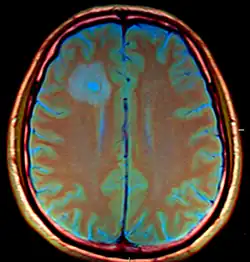

| Brain abscess in a person with a CSF shunt. The abscess is the darker gray region in the lower left of the image (corresponding to the right parietal lobe). The lateral ventricles are visible in black in the center of the brain, adjacent to the abscess.[1] | |

The diagnosis is established by a computed tomography (CT) (with contrast) examination. At the initial phase of the inflammation (which is referred to as cerebritis), the immature lesion does not have a capsule and it may be difficult to distinguish it from other space-occupying lesions or infarcts of the brain. Within 4–5 days the inflammation and the concomitant dead brain tissue are surrounded with a capsule, which gives the lesion the famous ring-enhancing lesion appearance on CT examination with contrast (since intravenously applied contrast material can not pass through the capsule, it is collected around the lesion and looks as a ring surrounding the relatively dark lesion). Lumbar puncture procedure, which is performed in many infectious disorders of the central nervous system is contraindicated in this condition (as it is in all space-occupying lesions of the brain) because removing a certain portion of the cerebrospinal fluid may alter the concrete intracranial pressure balances and causes the brain tissue to move across structures within the skull (brain herniation).[14]

Ring enhancement may also be observed in cerebral hemorrhages (bleeding) and some brain tumors. However, in the presence of the rapidly progressive course with fever, focal neurologic findings (hemiparesis, aphasia etc.) and signs of increased intracranial pressure, the most likely diagnosis should be the brain abscess.[15]